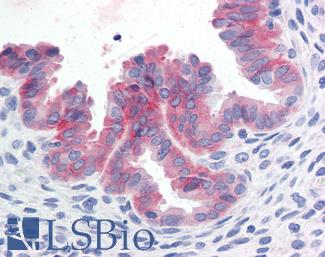

Progesterone Receptor / PGR

Anti-PGR / Progesterone Receptor antibody IHC of human uterus. Immunohistochemistry of formalin-fixed, paraffin-embedded tissue after heat-induced antigen retrieval. Antibody LS-B2983 concentration 20 ug/ml.